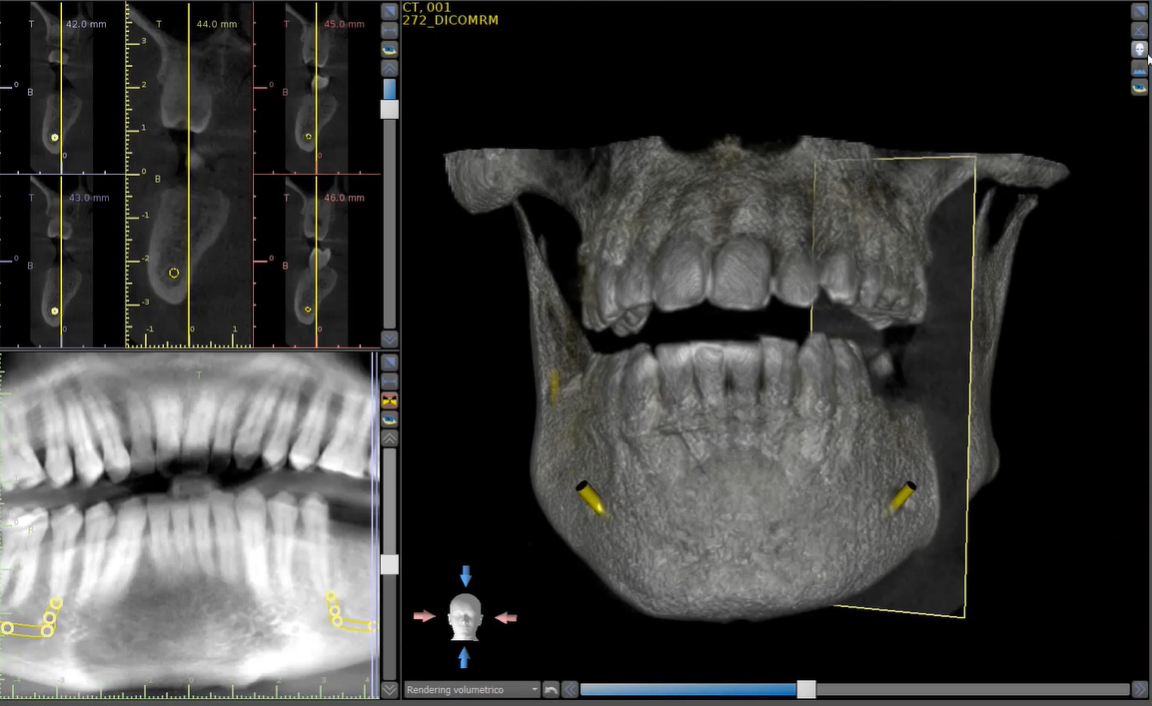

L'ortopantomografia o, più comunemente, “radiografia panoramica delle arcate dentarie”, è un esame radiologico che permette in modo non invasivo e non doloroso lo studio delle arcate dentarie e delle ossa mandibolari.

La Cone Beam 3D è una moderna metodologia diagnostica che consente di riprodurre sezioni o un'immagine del cranio tridimensionale che viene utilizzata, in genere, per l'implantologia.

Telecranio Latero-Laterale viene utilizzato per la progettazione ortodontica in tutti i tipi di pazienti, in particolare per i bambini.